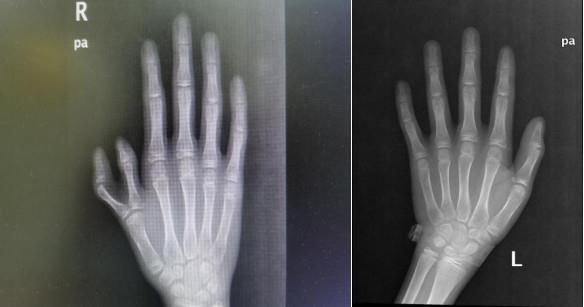

刚入院查症,男孩右手复拇指畸形,Wassel分型属IV型,呈蟹钳样,均较正常拇指细小。家属要求较高,并不满足于多余指切除矫形,科室组织专家讨论分析后,确定由梁再卿主任主刀,应用改良Bil-haut-Cloquet法行截骨矫形、指骨、关节、指甲成型术,即所谓的拼指,将两个细小的畸形指拼接成一个与正常拇指相仿的手指。

术前DR检查了解骨性结构,通常需要检查畸形指的正侧位,同样也要检查正常手对应指的正侧位,术前通过测量畸形指及正常拇指外观和指骨的直径、甲床的宽度等,通过测量数据分析设计切口及截骨量。